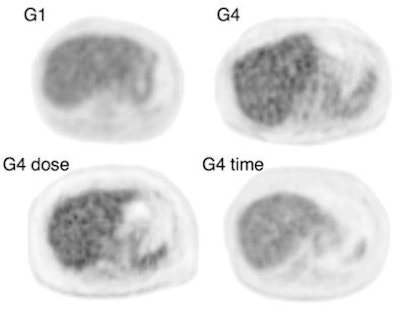

| PET/CT axial liver images show the image quality with average signal-to-noise (S/N) ratio for each patient group. S/N ratios of baseline group 1 (G1, lightest patients), baseline group 4 (G4, heaviest patients), group 4 with higher dose (G4 dose, heaviest group given dose), and group 4 with more scanning time (G4 time, heaviest patients) were 14.8, 8.5, 9.0, and 10.6, respectively. Images courtesy of the Journal of Nuclear Medicine. |

The researchers found that the S/N ratio of group 4 with the standardized scanning protocol was 8.5, whereas the S/N ratio of group 4 with a scanning time of five minutes per bed position was 10.6, a difference that was statistically significant.